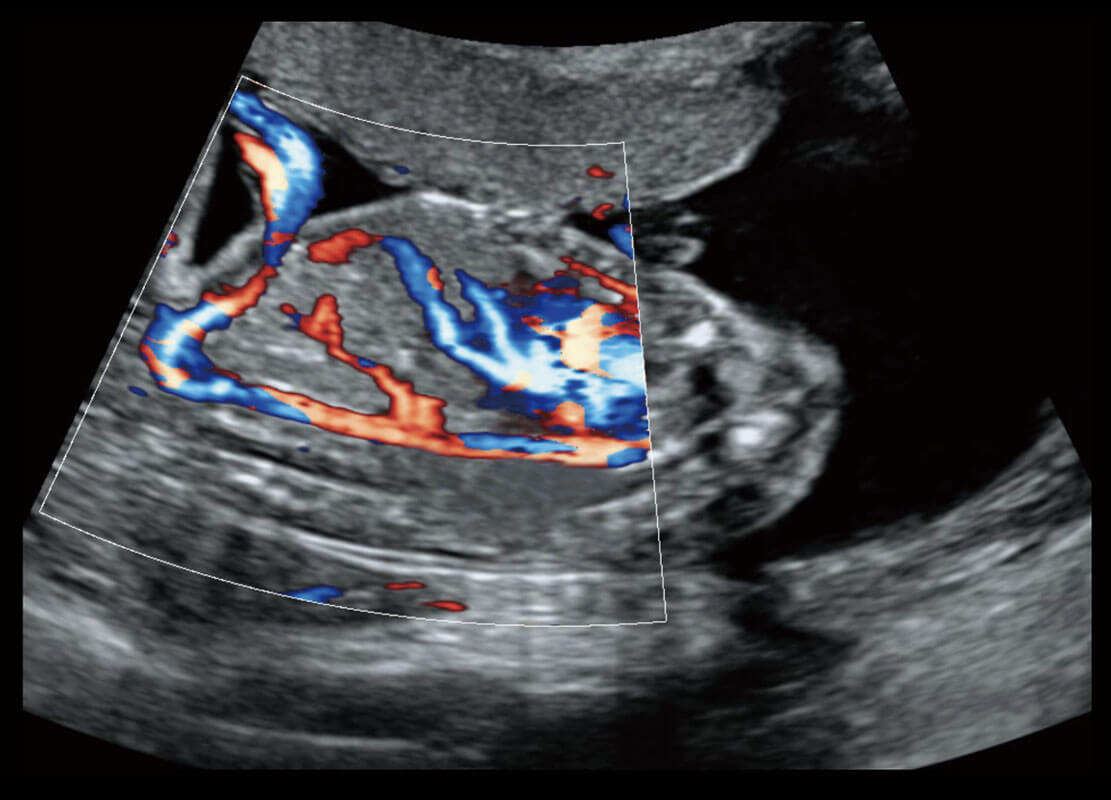

P60搭载宽频带线阵探头、宽景成像、弹性成像技术,为您提供乳腺应用方案。P60支持高频相控阵探头、线阵探头、腹部高频探头、腹部微凸探头等,丰富的探头群搭载敏感的彩色血流成像,适用于新生儿多种脏器检测要求,满足新生儿筛查需求。

新生儿肝血管癌